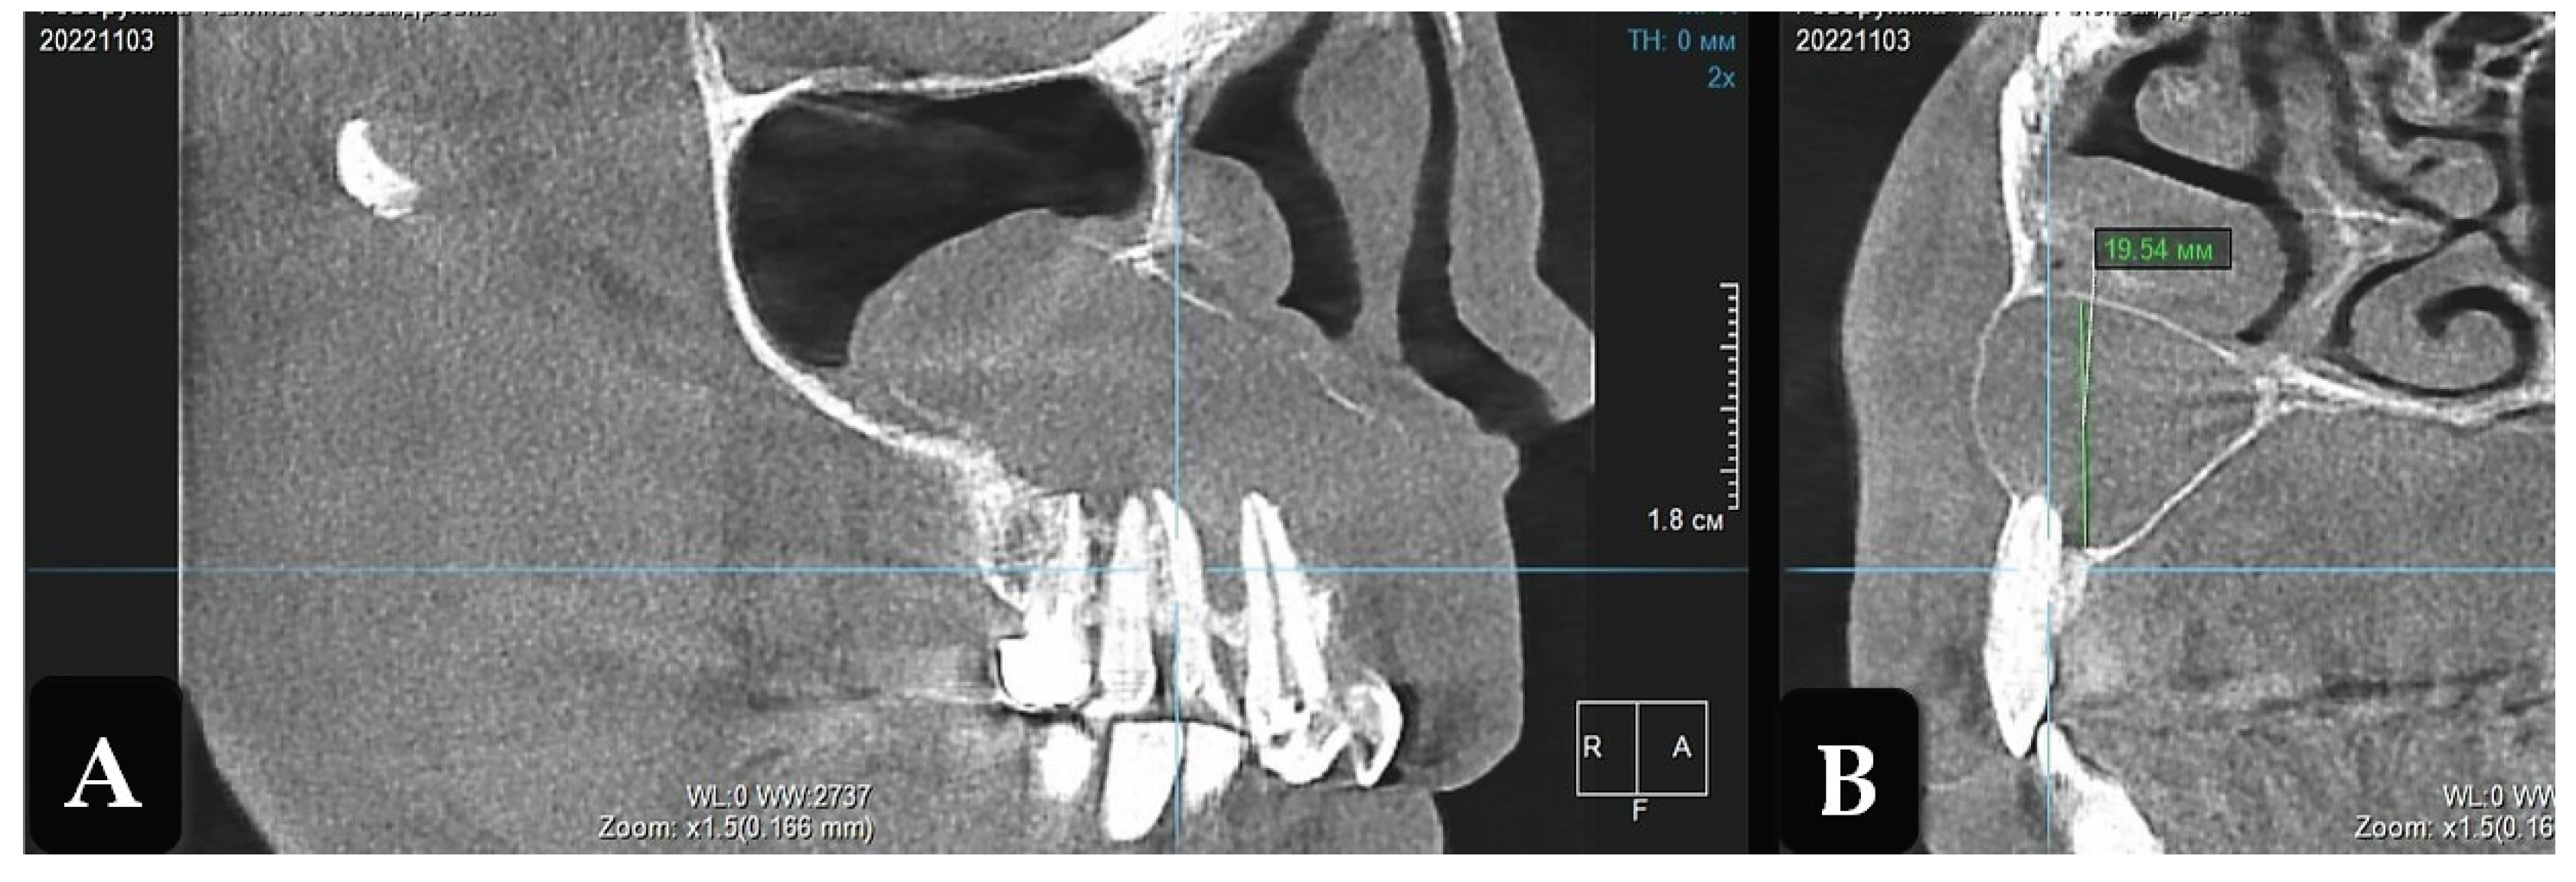

Two years after the operation, CBCT showed complete filling of the residual cavity with bone tissue to the level of the teeth roots, with beginnings of vestibular cortical formation. Separate sections of the cortical bone layer on the vestibular side at the level of teeth 1.2 and 1.1 were in the process of repair (Figure 5).

Figure 5. Cone-beam computed tomography. Residual bone cavity 2 year after enucleation of radicular cyst (projection of tooth 12). A: Frontal projection; B: Sagittal projection.